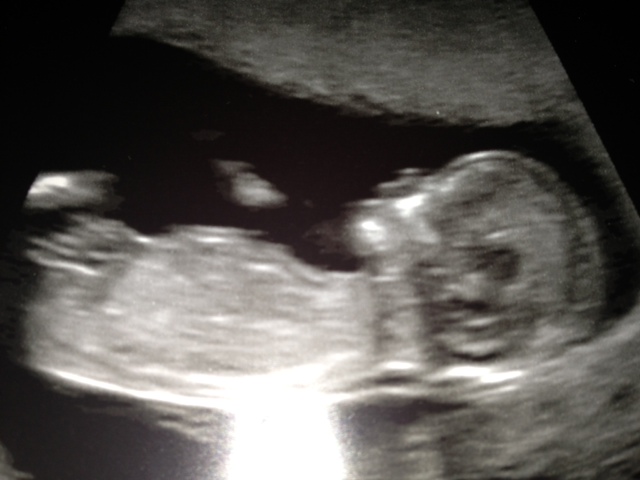

I posted this photo on another thread...just wondered if anyone could predict the sex of my little one. I have a feeling girl and I find out on Wednesday...any ideas? Thanks :-)Attachment 11824

Can't see a nub on this shot. Hope you get your DG.

I wonder which stripe is the nub? And what are those other stripes? Because depending on the stripe, I guess boy (top one) or girl (botton line) lol.

I think there may be a bit of cord happening down there.....but I think the bottom line may be the nub so I will ever so slightly guess girl....but I'm not overly confident!